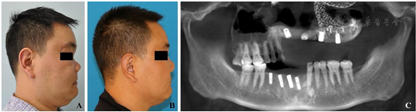

患者伤后13个月入院,本次手术主要解决鼻畸形、舌缺损以及种植牙的问题。全麻下行鼻畸形矫治术、舌尖成形术,上颌骨内固定装置取出术、种植体植入术。术中将肋软骨塑形后植入鼻根处,恢复鼻正常的外形,拆除上颌骨内固定装置后同时在上下颌植入种植体(图8,图9,图10)。术后给予抗感染及全身支持治疗,正常出院。

患者伤后17个月复诊,本次主要进行种植术后二期手术并对周围牙龈进行修整(图11)。种植体周围牙龈组织稳定后,上下颌取模制作种植义齿,恢复正常咬合关系,最终于伤后18个月完成所有治疗。